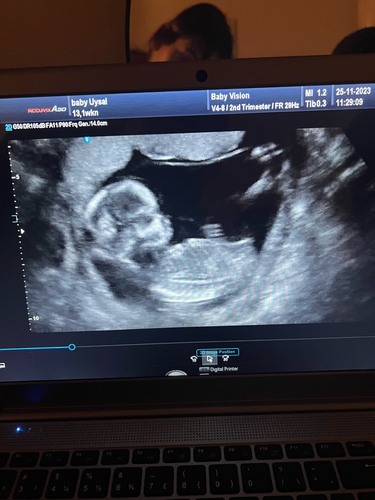

13 weken zwanger 馃挋馃┓?